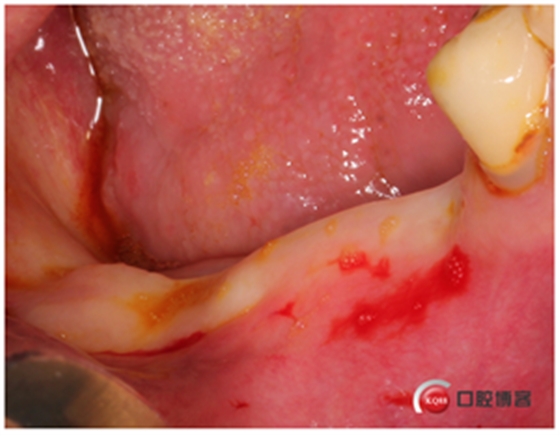

先操作容易的地方,把下頜先種了,這是技巧,如果你先做外提,技術(shù)又不是很熟練,光上頜就干了倆小時,患者還有耐心讓你再做下頜嗎?

修整牙槽嵴頂,切記從這時候開始所有取下來的骨頭都是寶貝。